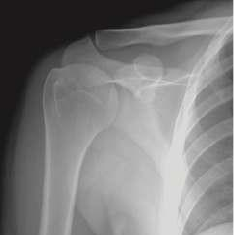

Medios de diagnóstico por imágenes: El estudio radiográfico del hombro puede estar

compuesto por proyecciones anteroposteriores en diferentes posiciones del brazo. La

combinación de estas imágenes permite evaluar los accidentes humerales, el ángulo lateral de la

escápula y el tercio lateral de la clavícula. Con esta proyección se pueden evidenciar las luxaciones de las articulaciones

acromioclavicular y glenohumeral o las fracturas de la epífisis proximal del húmero. El estudio radiográfico del brazo con proyección

anteroposterior permite buscar fracturas y cuerpos extraños en la región